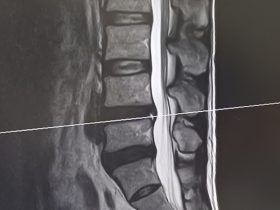

腰が痛いという訴えの中で一番多いのは、いわゆる「腰痛症」ですが、腰椎椎間板ヘルニアによる痛みはおよそ20~30%を占めています。 -

椎間板が潰れる、関節が狭くなる原因と症状

腰椎すべり症の原因と症状、治療法及びワンポイントストレッチ